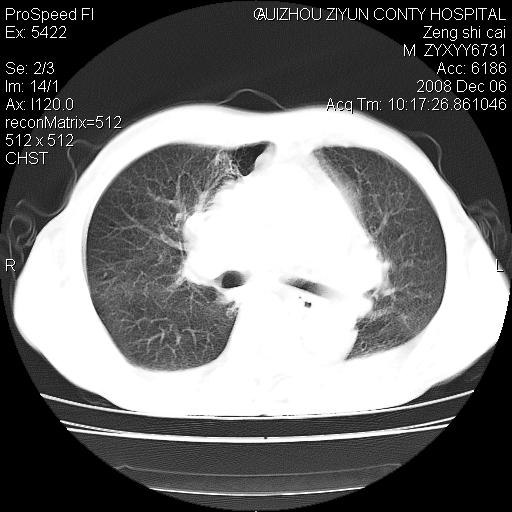

标题: CT16961:M、71岁,咳嗽半年,无血痰;胸片示右肺占位。 [打印本页]

标题: CT16961:M、71岁,咳嗽半年,无血痰;胸片示右肺占位。

右肺癌并纵隔淋巴结及胸膜转移可能性大

右肺癌并纵隔淋巴结及胸膜转移。建议气管镜

右肺纵隔型肺癌伴纵隔淋巴结及胸膜转移!

右肺纵隔型肺癌伴纵隔淋巴结转移!双侧胸水!

1)考虑右肺上叶纵隔型肺癌伴纵隔淋巴结转移。2)心包积液,双侧胸腔积液。

右肺癌并纵隔淋巴转移,腹膜后转移可能性大,两侧胸腔积液

右肺上叶纵隔型肺癌伴纵隔淋巴结转移。心包积液,双侧胸腔积液。

右上肺癌并纵隔淋巴结及胸膜转移。

建议强化!主要鉴别是淋巴瘤与肺癌淋巴结转移。

右肺纵隔型肺癌伴纵隔淋巴结及胸膜转移